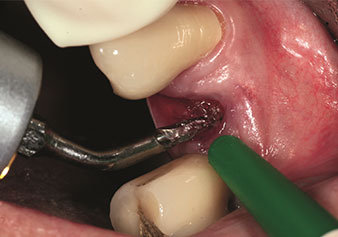

Indikation Interner Sinuslift

W&H bietet auch die perfekte Lösung für den internen Sinuslift an Nach der Kieferhöhlenpräparation mit dem

entsprechenden Instrumentarium (Abb. 3) erfolgt mit dem neuen Instrument Z35P (Abb. 4) die hydrodynamische Abhebung der Membran. Mit dem gleichen Instrumentenset kann auch die Implantatbett-Aufbereitung piezochirurgisch in aufsteigenden Durchmessern erfolgen (Abbildung drei und vier mit freundlicher Genehmigung von Dr. Mario Kirste, Frankfurt/Oder).